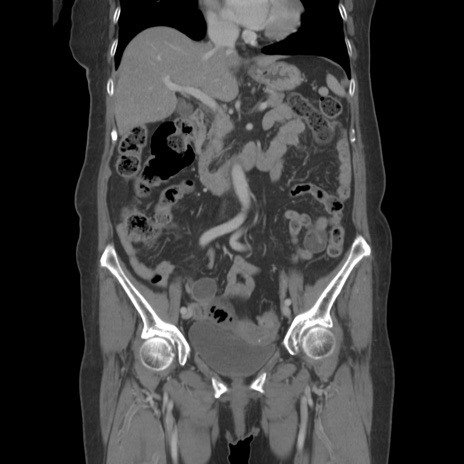

症例19(冠状断像)

【症例】80歳代女性

【主訴】下腹部痛

【現病歴】約8時間前より下腹部痛の出現あり、救急外来受診。

【既往歴】両側付属器切除

【身体所見】意識清明、下腹部正中に手術痕あり、その部位に一致して圧痛と反跳痛あり。腸蠕動音は亢進。

【データ】WBC 9300、CRP 0.15